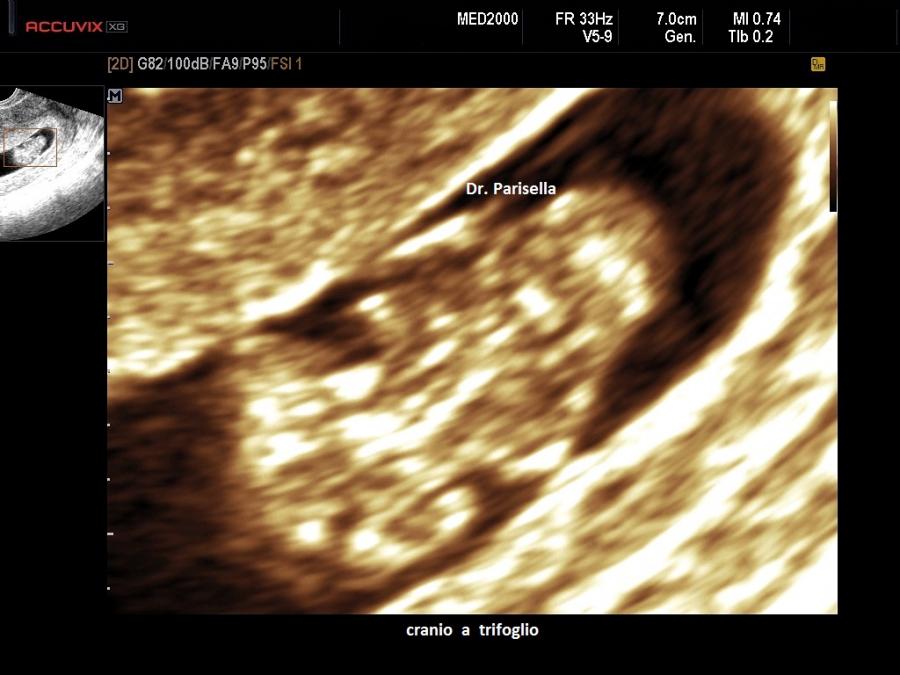

La Displasia Tanatofora tipo II è trasmessa con modalità autosomica dominante ed è caratterizzata da MICROMELIA SEVERA, IPOPLASIA TORACICA SEVERA e CRANIO A TRIFOGLIO.

Dal punto di vista ecografico la presenza contemporanea di MICROMELIA e CRANIO A TRIFOGLIO rappresentano una associazione di notevole rilevanza diagnostica per questa patologia.

Il cranio a trifoglio è evidenziabile in scansione coronale ed è dovuto alla sinostosi delle suture lambdoidea, coronale e sagittale e conseguente prominenza delle regioni temporali. Caratteristicamente in questi casi si ha molta difficoltà a misurare il Diametro Biparietale.